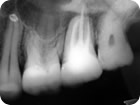

Retratamento Endodôntico

Retratamento Endodôntico 4